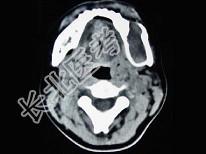

- 单项选择题男,28岁, 无意中发现左下颌骨较对侧隆起,CT如图所示, 最可能的诊断是 ( )

A、下颌骨齿釉细胞瘤

B、下颌骨巨细胞瘤

C、下颌骨角化囊肿

D、下颌骨根端囊肿

E、下颌骨含牙囊肿